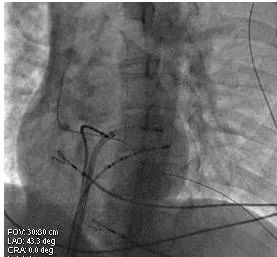

14.确定靶点后,逆钟向旋转大头,腔内电图示小A大V,AV比例1:4,温控30W、55℃放电60 s,心室起搏验证旁道阻断,若阻断,巩固放电120s。(见图2)

图2. 左前斜位观消融大头位于二尖瓣环游离壁